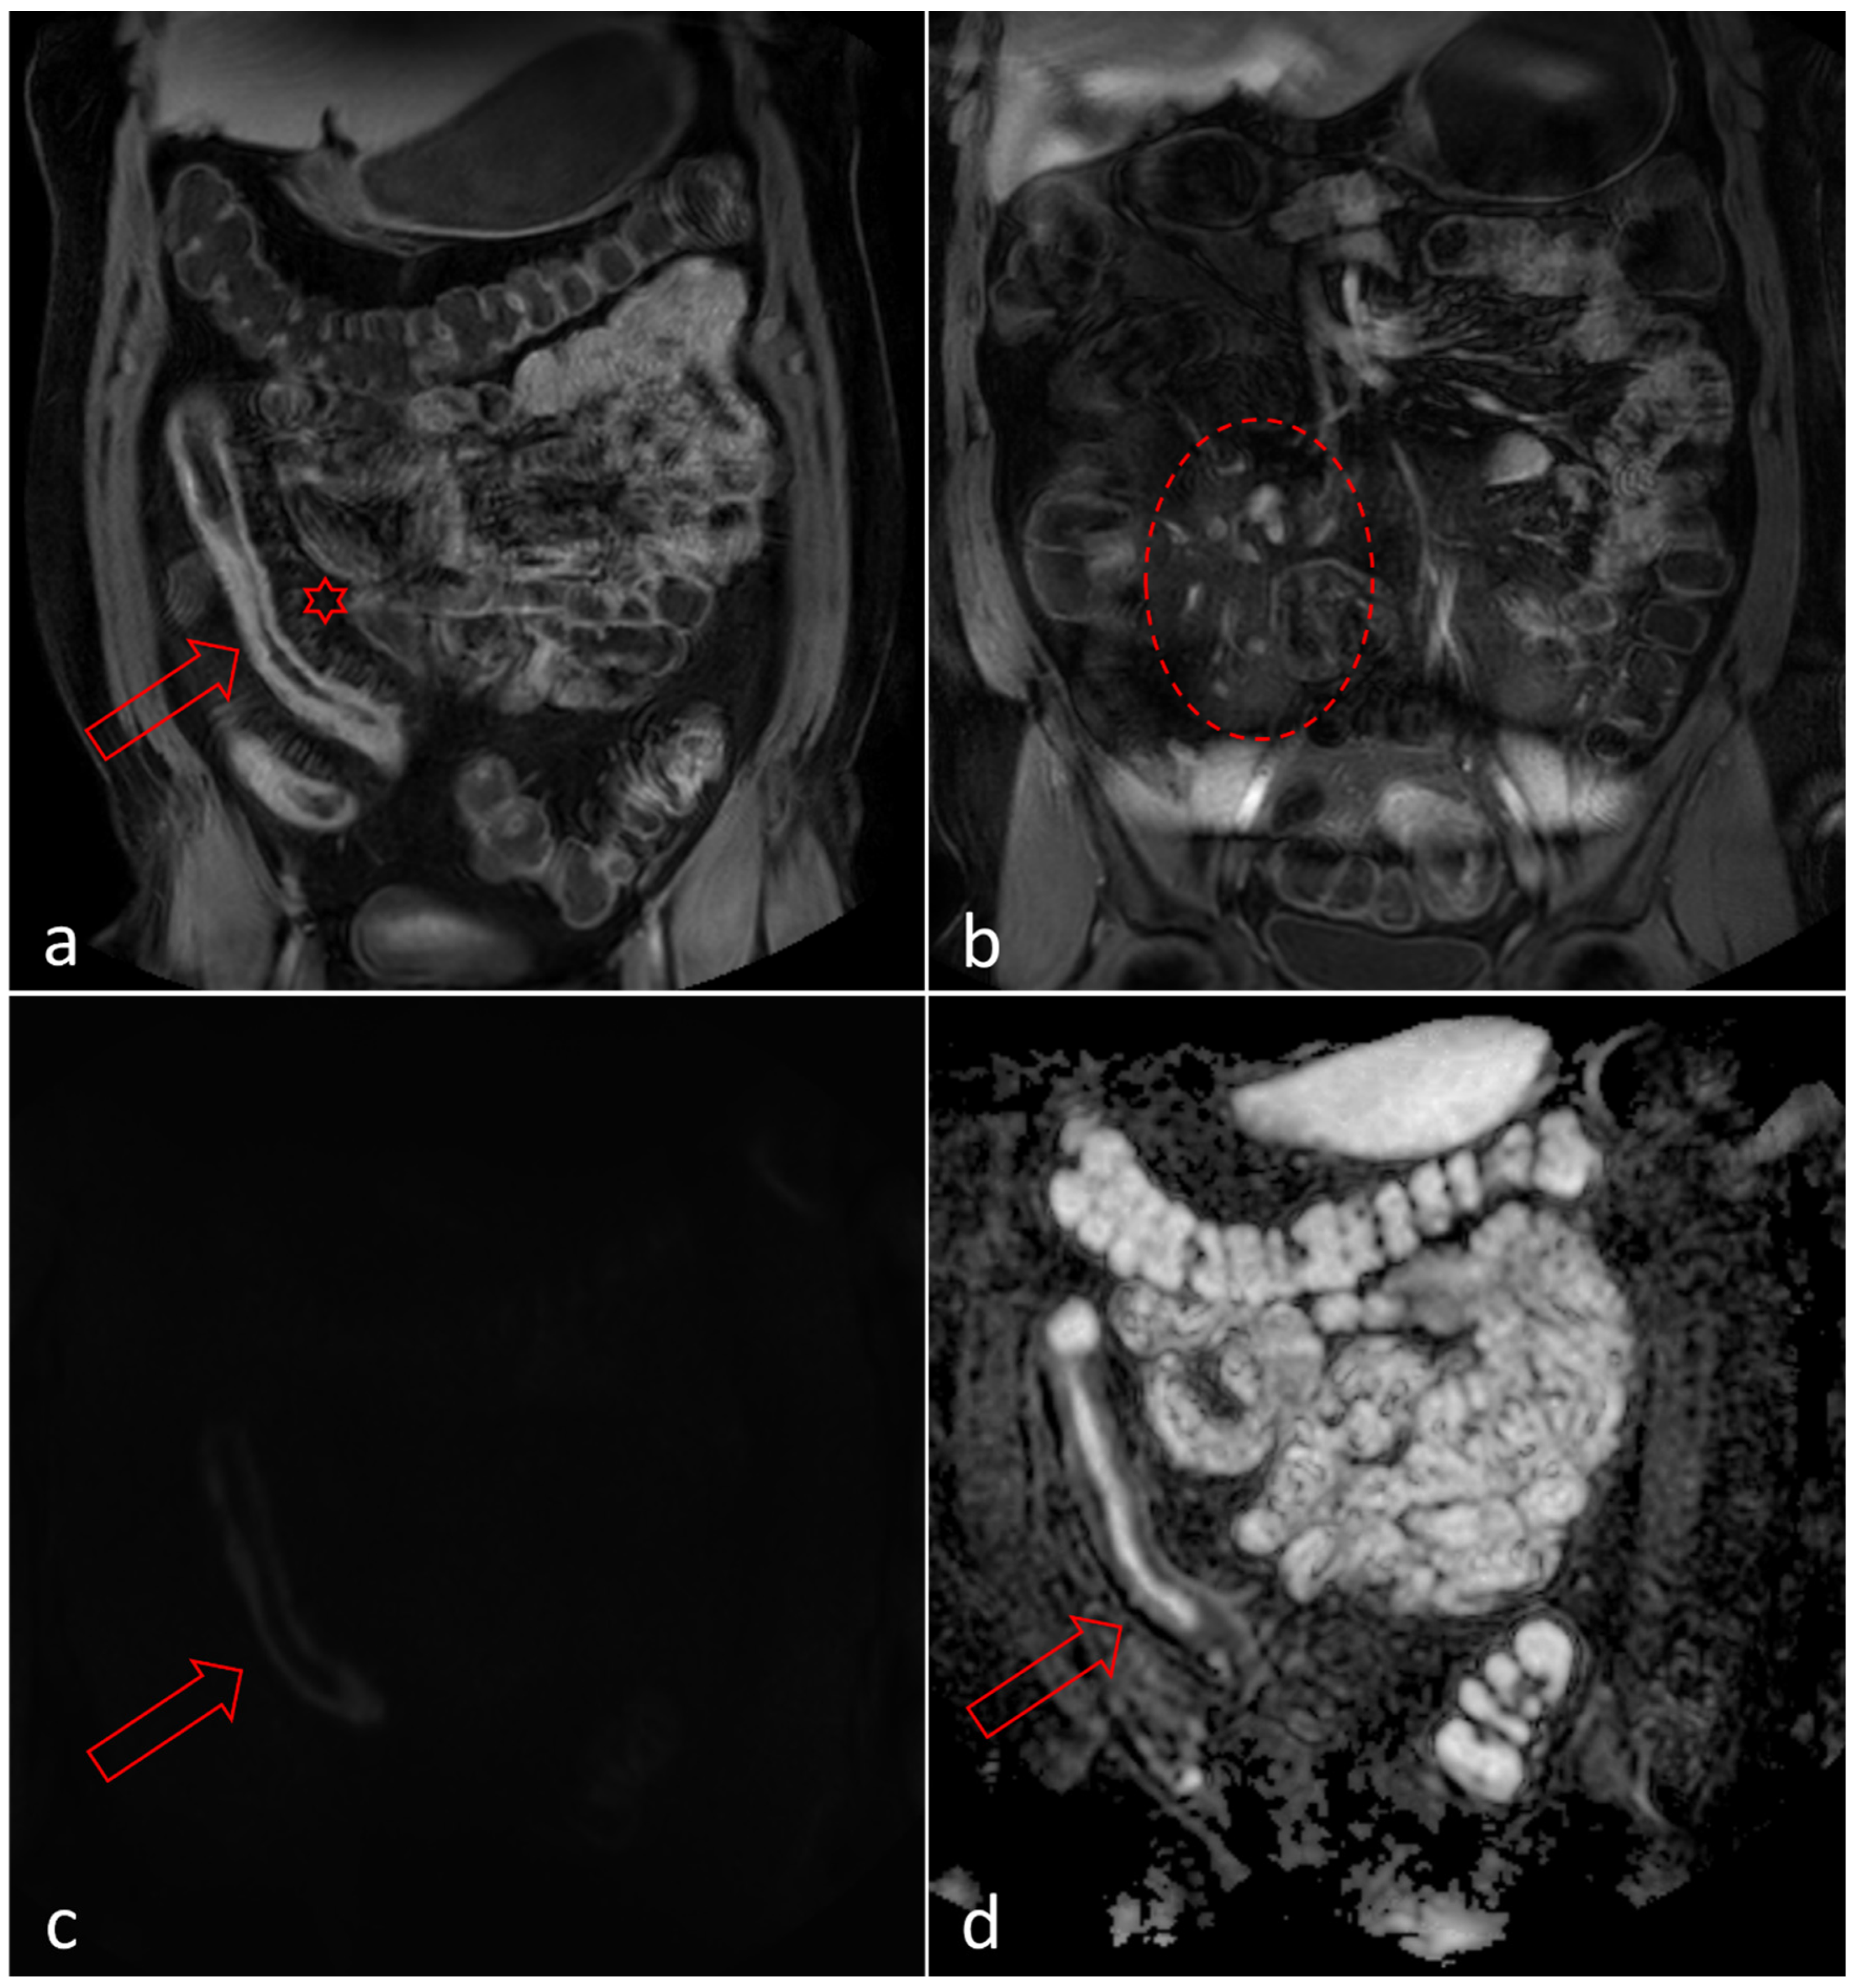

2.4. Magnetic Resonance Enterography